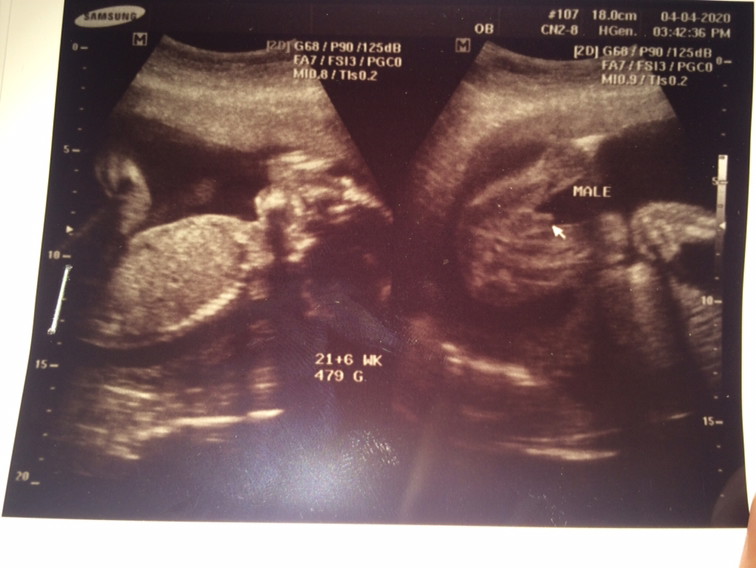

ผู้ชายค่ะ 🥰🥰🥰🥰🥰🥰🥰🥰🥰

บ้านนี้ได้ผู้ชายคะ 👶🏻